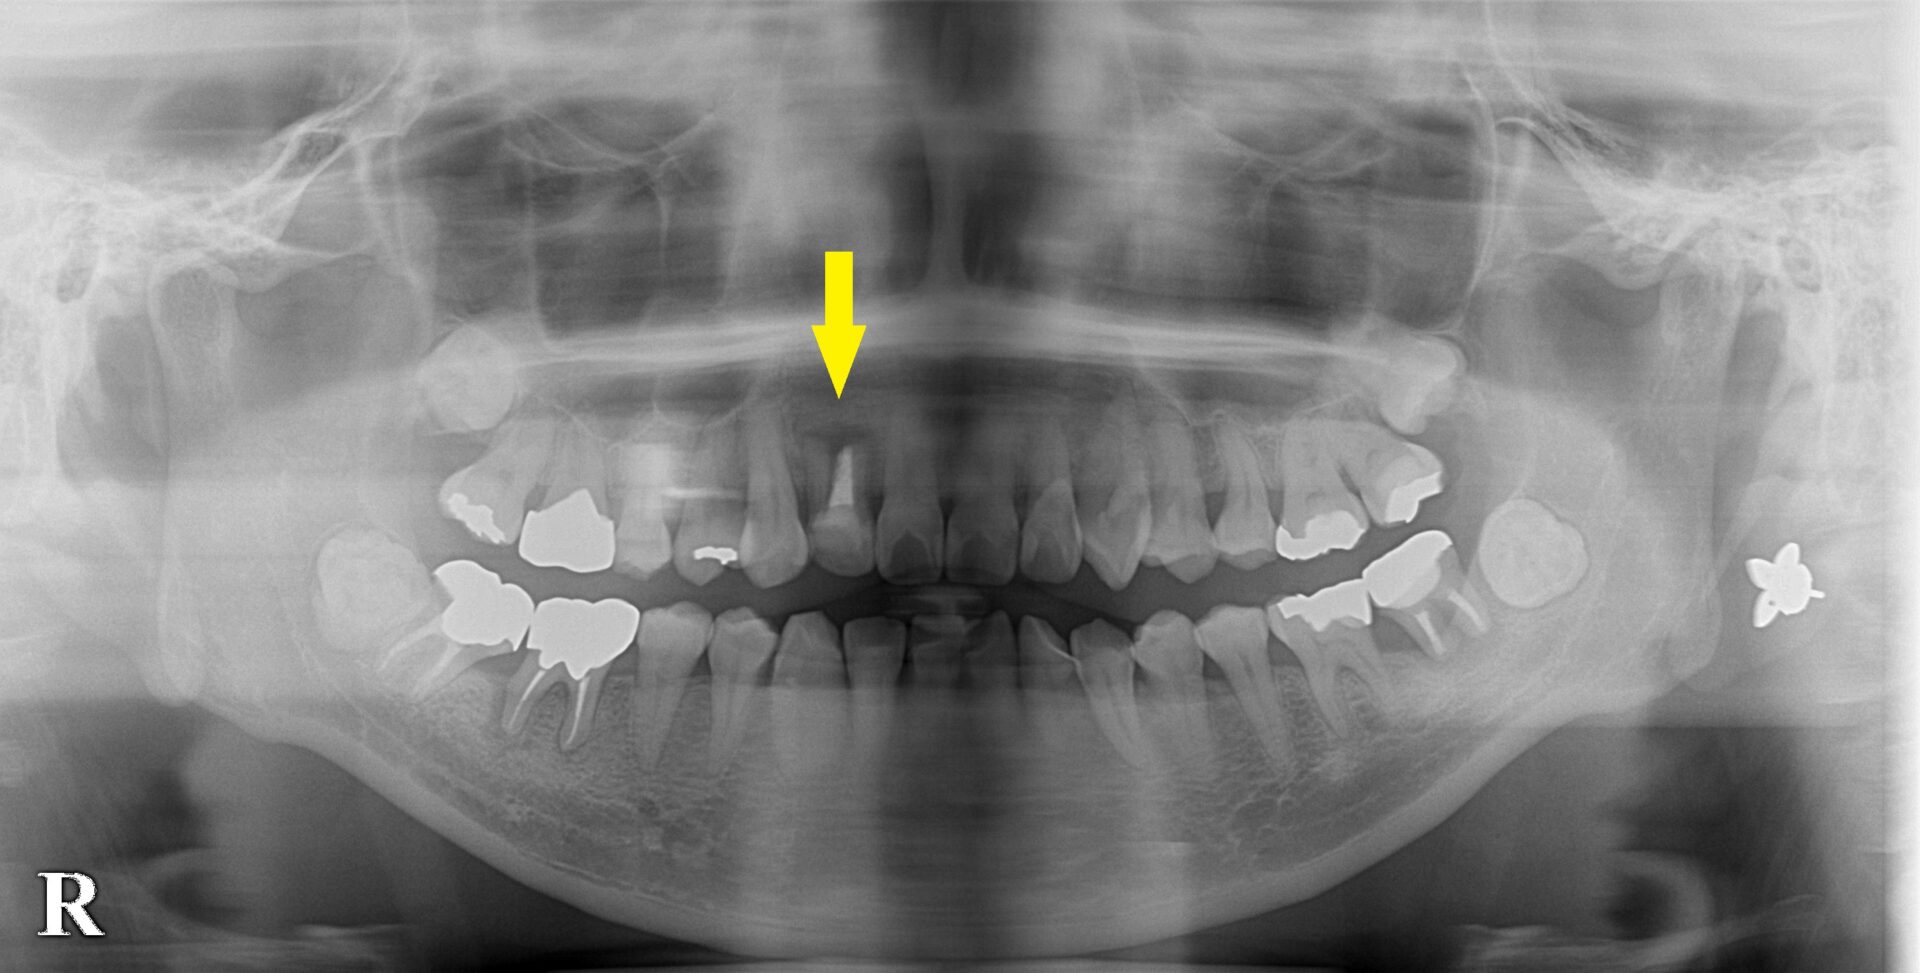

CTを見てみると、確かに歯を支える骨が、歯根の先まで吸収されてしまっていました(下の写真中段)。

この場合、人工骨を用いた骨造成術を併用することで、インプラントの埋入が可能であると説明させていただき、

了承いただけましたので、本日、インプラントの埋入と同時に、骨造成術を施行しました。

下の写真下段が手術後のCTになります。